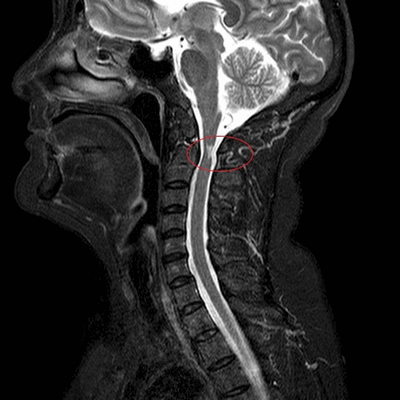

МРТ шеи: оценка сколиоза (коронарная плоскость, Т2 последовательность, STIR)

МРТ шейного отдела позвоночного столба: сколиоз (коронарная плоскость, Т2 ВИ)